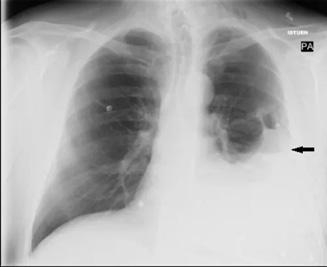

Figura 1. Opacidades difusas en espacios aéreos

Figura 3. Radiografía de tórax en paciente con asbestosis